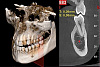

Высококачественная 2D-визуализация, полученная с помощью множества расширенных функций для более эффективной диагностики. Он обеспечивает детализацию изображений благодаря чувствительности недавно разработанного CMOS сенсора. GO 2D/3D предлагает быструю и точную диагностику с помощью нескольких программных опций для сбора изображений, предназначенных для получения высококачественных 2D-изображений для всех диагностических нужд. Отличные, четкие и подробные панорамные изображения с технологией ApT (Авто адаптивные обработки изображений). Функция aPAN (адаптивное панорамирование) позволяет получать пять слоев панорамных изображений за одно сканирование, чтобы выбрать наиболее подходящее для объема исследования.Совершенство в 3D

NewTom GO генерирует выдающиеся объемные изображения и для каждого FOV в диапазоне от 6х6 до 10х10 см. Выбор из 3 протоколов позволяет адаптировать требуемую дозу рентгеновского излучения к конкретным потребностям: от очень низкой для быстрого сканирования, необходимого при последующих хирургических проверках, до регулярной для планирования лечения, до очень высокого уровня детализации для анализа микроструктур.Минимальная доза, максимальное диагностическое качество

2D визуализация максимального качества благодаря многим продвинутым функциям для более эффективной диагностики

Вы получаете детализированные изображения благодаря чувствительности новейшего датчика CMOS. GO 2D/3D предлагает быструю и точную диагностику с несколькими программными вариантами получения снимка, разработанными для съемки высококачественных 2D изображений для любых диагностических задач. Отличные, четкие и подробные панорамные изображения благодаря технологии ApT (автоадаптивная обрботка картинки). Функция aPAN (адаптивное панорамирование) позволяет снимать пять слоев панорамных изображений за одно сканирование и выбрать наиболее подходящее для цели обследования.

Детализированные объемы для всех клинических задач с заботой о здоровье пациентов

NewTom GO создаёт выдающиеся объемные изображения для каждого поля обзора, от 6*6 до 10*10 см. Выбор из 3 протоколов позволяет устанавливать дозу излучения, требуемую для конкретной задачи: от очень низкой для быстрого сканирования при хирургическом наблюдении, средней для планирования лечения, до очень высокого уровня детализации для анализа микроструктур.